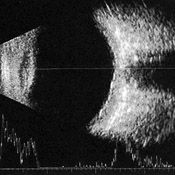

2.ECOGRAFIE OCULARA

Ecografie oculara este un examen care studiaza structurile oculare mascate de un mediu netransparent, cum este de exemplu mascarea retinei de catre o cataracta care opacifiaza cristalinul. Aceasta permite de asemenea masurarea dimensiuniii globului ocular si studierea diferitelor structuri ale orbitei, in mod special nervul optic, si muschii oculomotori. Ecografie oculara este nedureroasa si nu se insoteste de efecte secundare. Ultrasunetele nu reprezinta un pericol pentru ochi. Rezultatele se cunosc imediat.